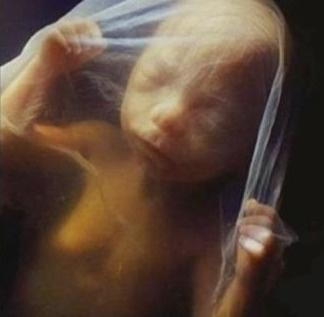

Εννέα μήνες μετά θα έχετε ένα αξιολάτρευτο αγοράκι που θα το ντύσετε με όμορφα αγορίστικα ρούχα.